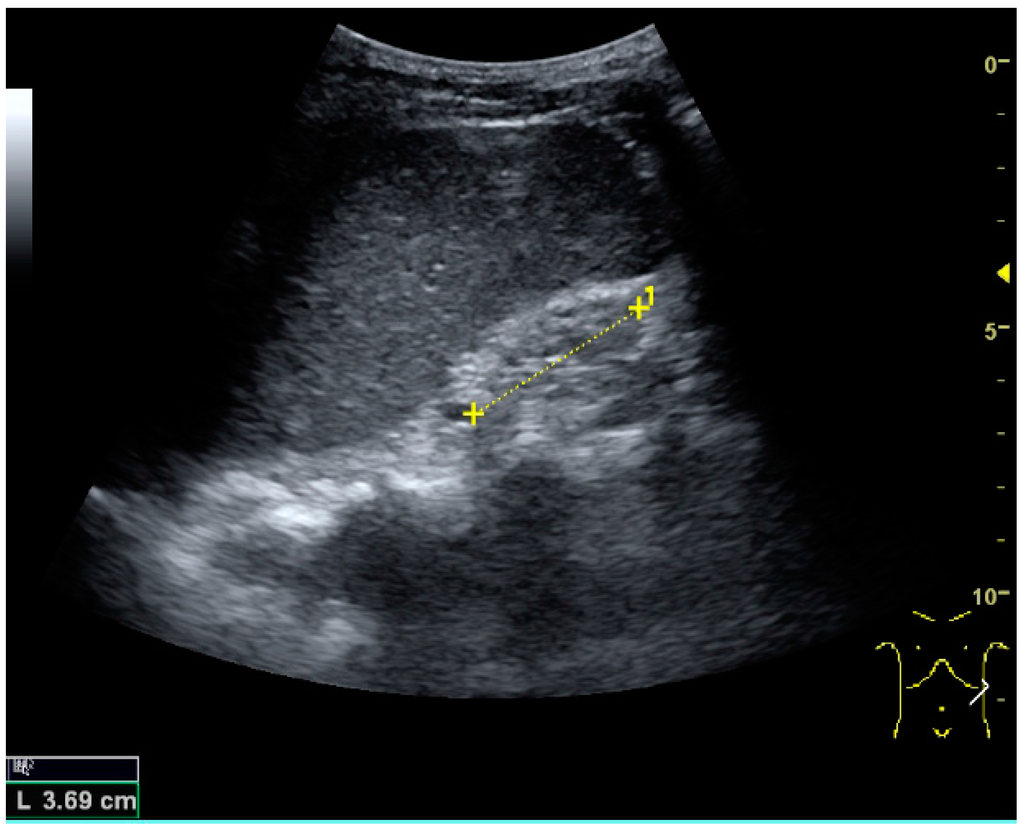

US is useful for diagnostic and prognostic purposes in chronic kidney disease. Whether the underlying pathologic change is glomerular sclerosis, tubular atrophy, interstitial fibrosis or inflammation, the result is often increased echogenicity of the cortex. The echogenicity of the kidney should be related to the echogenicity of either the liver or the spleen (Figure 22 and Figure 23) [2]. Moreover, decreased renal size and cortical thinning are also often seen and especially when disease progresses (Figure 24 and Figure 25). However, kidney size correlates to height, and short persons tend to have small kidneys; thus, kidney size as the only parameter is not reliable [2].

Figure 24. Chronic pyelonephritis with reduced kidney size and focal cortical thinning. Measurement of kidney length on the US image is illustrated by ‘+’ and a dashed line.